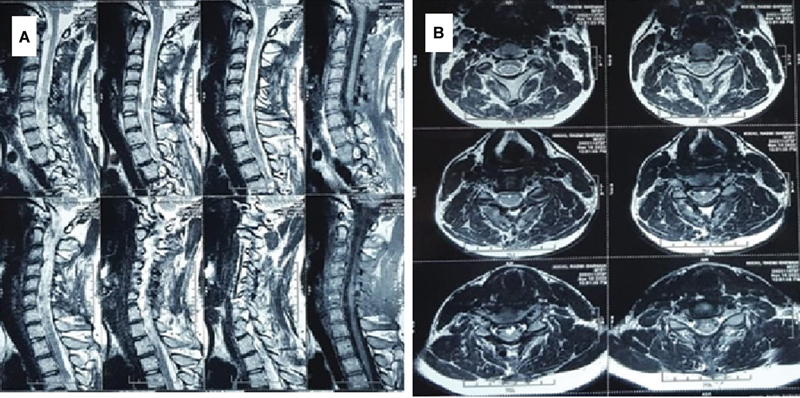

An arachnoid cyst is mostly congenital CSF-filled space occurring in the brain and spine. In the spine, they are usually found in the posterior aspect. Anterior cervical arachnoid cyst is very uncommon. A 14-year-old adolescent boy presented with rapidly progressive quadriparesis starting with the left lower limb, which is associated with radiating pain and numbness in both upper extremities. There was no sensory deficit, and the bladder and the bowel were normal. The radiological evaluation with contrast-enhanced MRI was suggestive of an anterior cervical intradural arachnoid cyst, for which the patient underwent surgery with wide fenestration and partial removal of the cyst wall, and the cyst wall was sent for histopathological examination. The patient improved postoperatively without any residual deficit. Anterior cervical arachnid cyst is a very rare lesion and should be considered in children and young adults who presented with neck pain or radiculopathy, especially if they are followed by motor weakness.